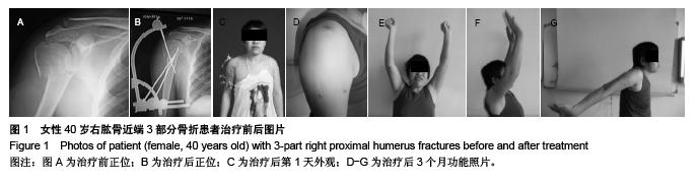

Novel closed intersection nailing external fixation repairs proximal humerus fractures: 6-month follow-up

Huang Hai-jing, He Jin-quan, Wang Jie, Jin Hong-bin. Novel closed intersection nailing external fixation repairs proximal humerus fractures: 6-month follow-up[J]. Chinese Journal of Tissue Engineering Research, 2015, 19(48): 7795-7800.